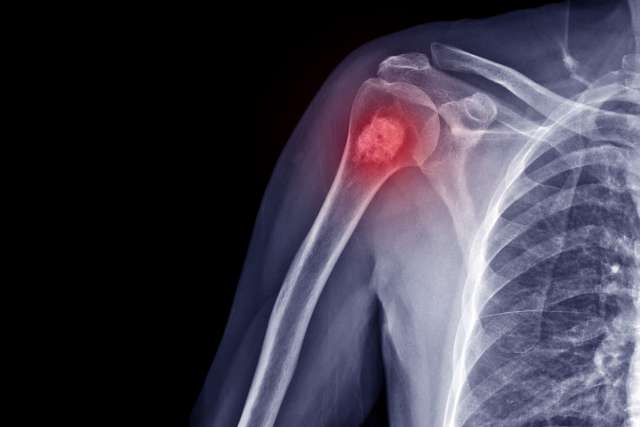

Malignant Bone Tumors

Cancerous growths that start in or spread to bones, including:

Osteogenic sarcoma (osteosarcoma): Cancer that starts in the bone cells, often developing at the ends of bones where new tissue forms as children grow